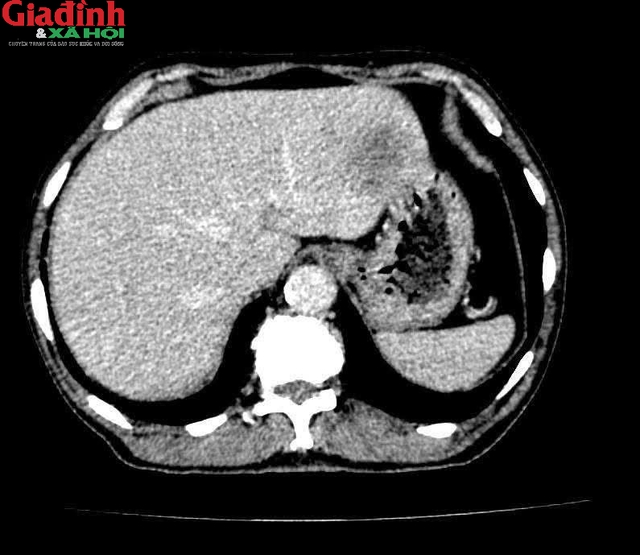

Bệnh nhân T.X.T (73 tuổi) có tiền sử tăng huyết áp, đái tháo đường type II, di chứng liệt nửa người sau tai biến mạch máu não và viêm gan B. Sau khi thăm khám bằng các phương pháp cận lâm sàng như chụp CT, MRI và nội soi dạ dày – đại tràng, các bác sĩ Bệnh viện 19-8 xác định người bệnh bị ung thư đại tràng phải đã di căn sang gan trái.

Các bác sĩ xác định người bệnh bị ung thư đại tràng phải đã di căn sang gan trái.